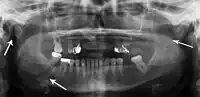

Panoramic radiography

Panoramic radiographs are tomograms where the mandible is in the focal trough and show a flat image of the mandible. Because the curve of the mandible appears in a 2-dimensional image, fractures are easier to spot leading to an accuracy similar to CT except in the condyle region. In addition, broken, missing or malaligned teeth can often be appreciated on a panoramic image which is frequently lost in plain films. Medial/lateral displacement of the fracture segments and especially the condyle are difficult to gauge so the view is sometimes augmented with plain film radiography or computed tomography for more complex mandible fractures.

- Panoramic radiograph of a simple mandible fracture of the right mandibular body, minimally displaced. Note that the teeth to the left of the fracture do not touch